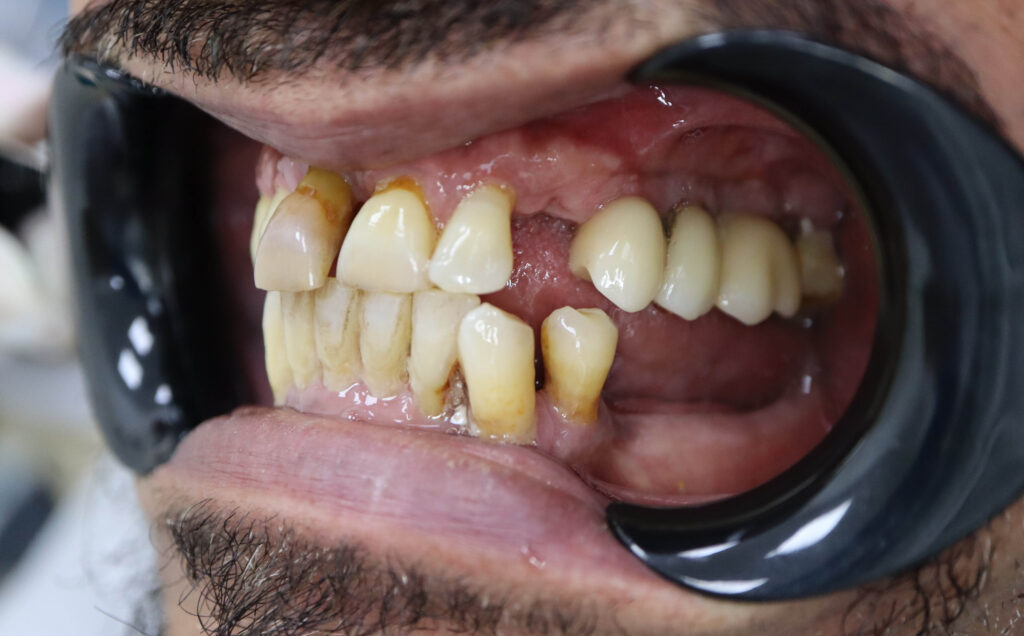

Ситуация до лечения

Пациент обратился с жалобами на эстетические недостатки.

У пациента уже стояло некоторое количество имплантатов. Было решено использовать их при протезировании.

пациент до имплантации